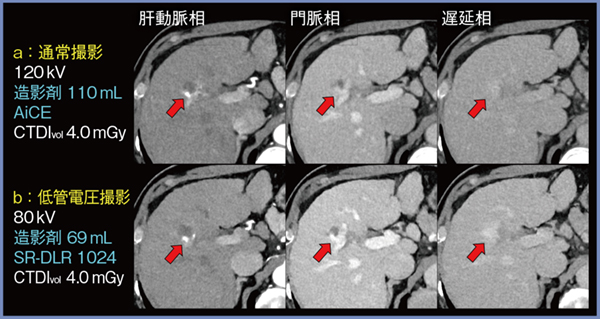

SR-DLR 1024は,腎機能障害がある患者の低管電圧撮影にも有用である。症例2は,60歳,男性,肝硬変・肝血管腫の症例である。通常の肝ダイナミックプロトコール(120kV,造影剤110mL,AiCE適用)の画像(図4 a)に対し,SR-DLR 1024を適用した低管電圧撮影(80kV)の画像(b)では,造影剤量を約4割低減(69mL)しているにもかかわらずヨードのコントラストは向上しており,ノイズも低いレベルで保たれている。血管腫による淡い遅延性造影効果もより明瞭である(図4↑)。また,肝表部分に着目すると,肝硬変に伴う結節状の不整像がSR-DLR 1024にてより明瞭に描出され,肝線維化の重症度評価にも有用と考えられた。

図4 症例2:肝硬変・肝血管腫(60歳,男性)